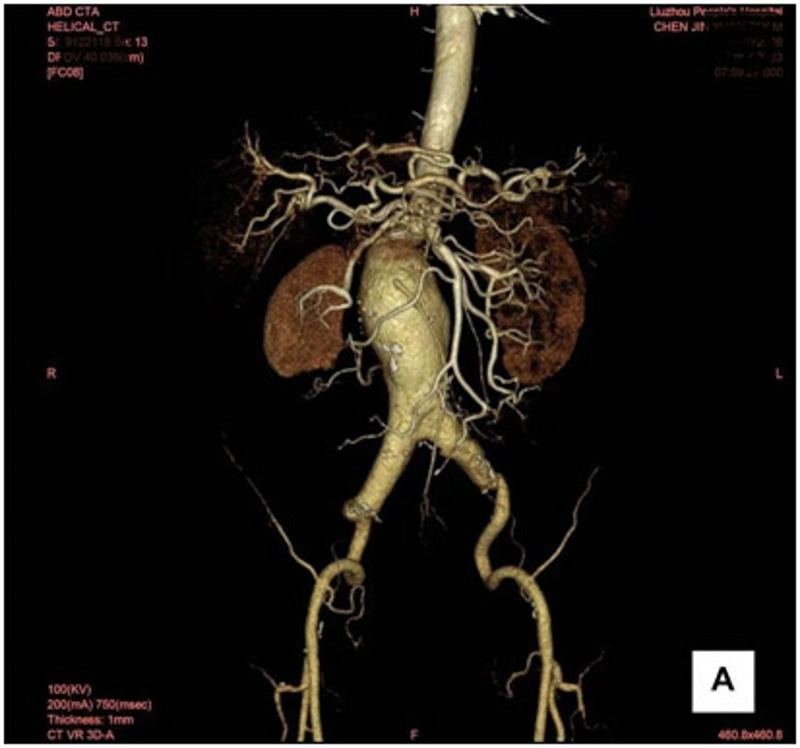

市民陳老伯(化名)已年過(guò)七旬,近日因腹痛難忍,被家屬送至柳州市人民醫(yī)院就診。醫(yī)生經(jīng)腹部增強(qiáng)CT檢查,診斷為復(fù)雜型腹主動(dòng)脈瘤,已累及腎動(dòng)脈。

柳州市人民醫(yī)院血管外科主任霍鑫了解患者情況后,立刻召集團(tuán)隊(duì)專(zhuān)家開(kāi)展討論。腹主動(dòng)脈瘤累及內(nèi)臟動(dòng)脈一直是腹主動(dòng)脈瘤腔內(nèi)治療難點(diǎn),再加上患者年事已高,手術(shù)風(fēng)險(xiǎn)將變得非常大。患者腹主動(dòng)脈瘤頸離左腎動(dòng)脈開(kāi)口只有8mm, 既要封堵住腹主動(dòng)脈瘤,又要保證左腎動(dòng)脈的正常血供,血管外科決定采用創(chuàng)傷小、恢復(fù)快、預(yù)后好的覆膜支架體外“開(kāi)窗”腔內(nèi)隔絕術(shù)為患者治療。